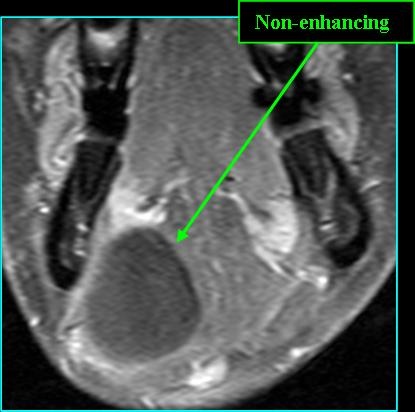

Radiologic Findings

- On MR: low signal on T1; very high signal on T2; T1 post-contrast shows wall enhancement and high signal if infection present